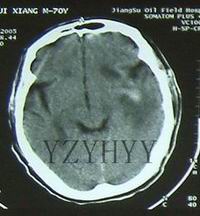

(2)cT掃描不僅可以直接顯示血腫大小和部位,還可以了解腦室受壓和中線結構移位的程度及並存的腦挫裂傷、腦水腫等情況,應及早套用於疑有顱內血腫患者的檢查。硬腦膜外血腫cT表現為顱骨內板與硬腦膜之間的雙凸鏡形或弓形高密度影;急性或亞急性硬腦膜下血腫cT表現為腦表面新月形高密度、混雜密度影,多伴有腦挫裂傷和腦受壓;腦內血腫表現為腦挫裂傷區附近或腦深部白質內類圓形或不規則高密度影。

顱內血腫--CT(1)、手術治療可根據CT所見採用骨瓣或骨窗開顱,清除血腫,妥善止血。血腫清除後,如硬腦膜張力高或疑有硬膜下血腫時,應切開硬膜探查。對少數病情危急,來不及做CT等檢查者,應直接手術鑽孔探查,再擴大成骨窗清除血腫。